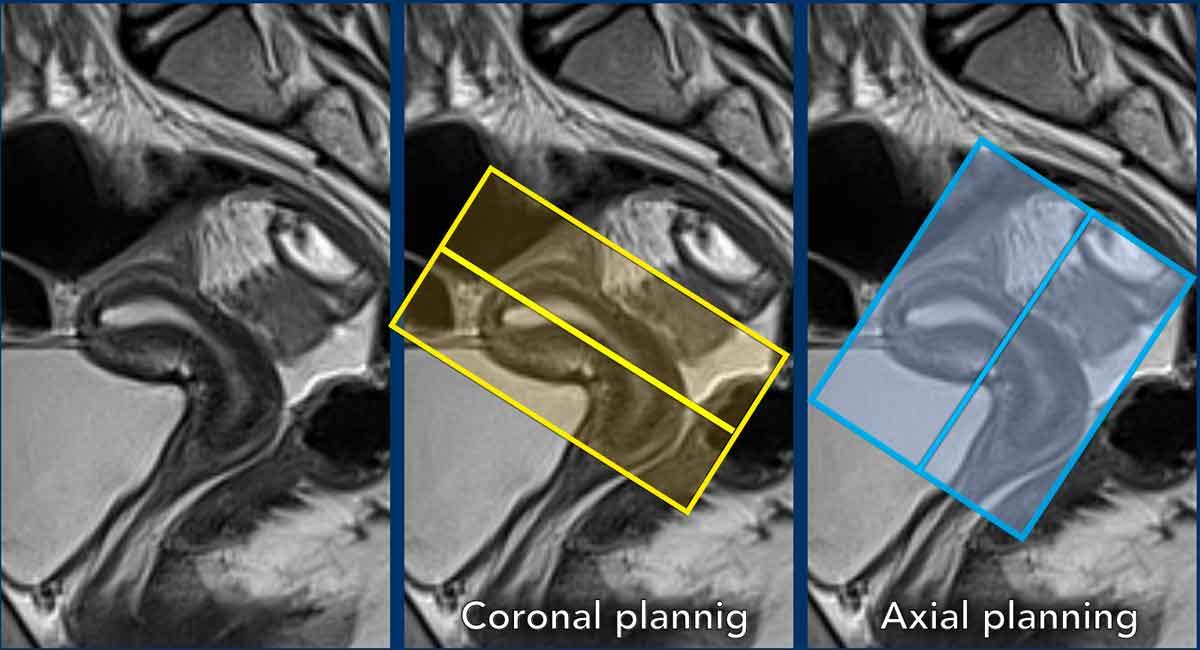

Lập kế hoạch chuỗi xung

Các chuỗi xung MRI được lập kế hoạch dựa trên trục dài của buồng tử cung.

Mặt phẳng trục vuông góc với trục dài của buồng tử cung.

Mặt phẳng vành song song với trục dài.

Lưu ý: các biến thể trong giải phẫu tử cung

Cần tính đến vị trí của tử cung và lập kế hoạch các chuỗi xung MRI vuông góc và song song tương ứng.

Trong trường hợp này, cổ tử cung ở tư thế ngả trước và thân tử cung ở tư thế gập sau.

Chuỗi ảnh mặt phẳng vành được lập kế hoạch song song với buồng tử cung (ô vàng), trong khi chuỗi ảnh mặt phẳng trục được lập kế hoạch vuông góc với nó (ô xanh lam).

Đây là một ví dụ khác cho thấy cổ tử cung ở tư thế ngả sau và thân tử cung ở tư thế gập trước.

Hãy quan sát cách biến thể vị trí này ảnh hưởng đến việc lập kế hoạch chuỗi xung tương ứng.